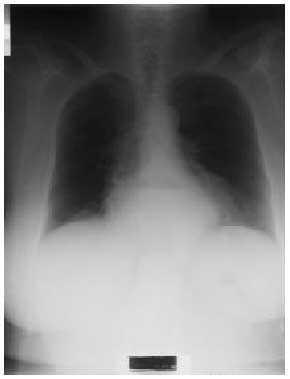

Fig. 1.

A la exploración no se encuentran hallazgos destacables, objetivándose un murmullo vesicular conservado con alguna sibilancia ocasional espiratoria, a 18 respiraciones/min, con una auscultación cardíaca y resto de exploración física normal. Se refuerza el tratamiento broncodilatador y antiinflamatorio inhalado de la paciente sin que se objetive mejoría alguna tras 2 semanas, por lo que al no existir cambios en el cuadro clínico se decide solicitar una radiografía anteroposterior y lateral de tórax, así como una analítica general.

La radiografía de tórax evidencia una imagen redondeada con nivel hidroaéreo, retrocardíaca, compatible con gran hernia de hiato. La analítica de sangre no demuestra ninguna alteración. Dados los hallazgos radiológicos, se reinterroga de nuevo a la paciente, que refiere cuadros ocasionales de pirosis posprandrial, con sensación de plenitud y malas digestiones habituales que suele paliar con antiácidos, así como crisis de tos después de las comidas en las últimas semanas. Ante la sospecha de enfermedad por reflujo gastroesofágico (ERGE), se recomiendan medidas higiénico-dietéticas y se instaura tratamiento con inhibidores de la bomba de protones, mejorando la sintomatología en algunas semanas. Se solicita un tránsito esofagogastroduodenal, que se informa como hernia de hiato manifiesta, sin posibilidad de conocer la existencia de lesiones en la mucosa, puesto que la paciente se niega a la realización de la endoscopia.